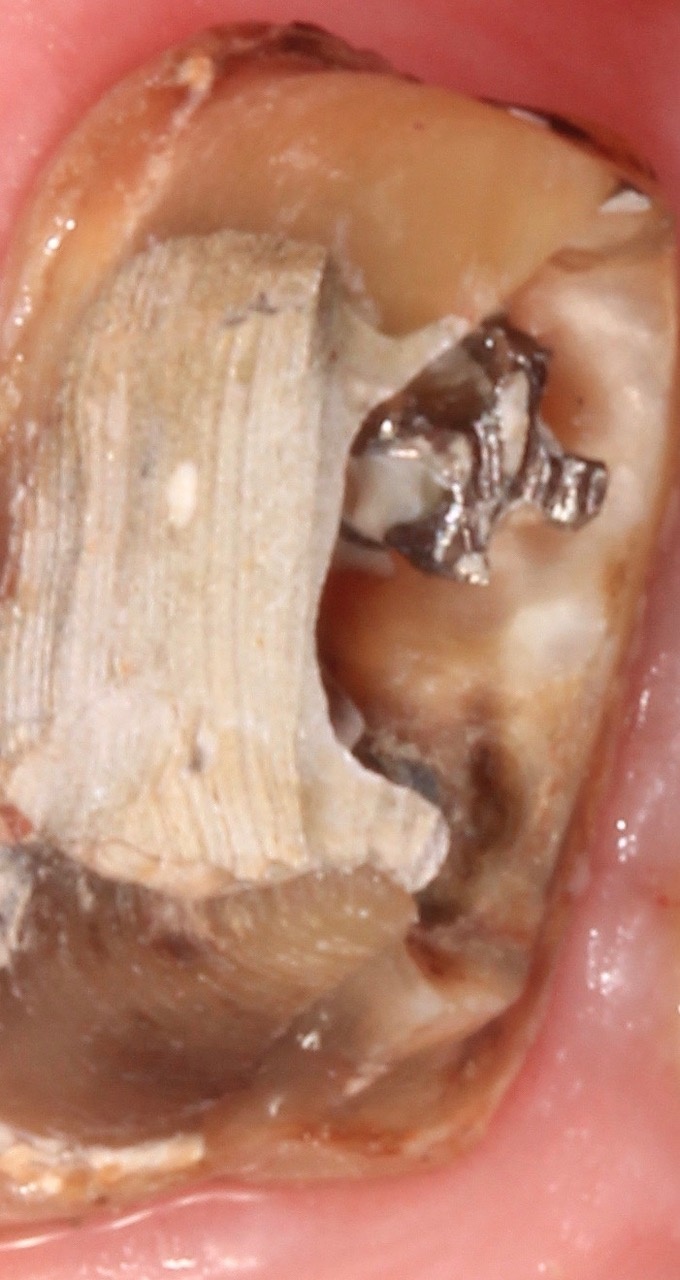

Nach ausführlicher Aufklärung der vorhandenen Therapiealternativen entschied sich der Patient für die Revisionsbehandlung. Diagnostisch wichtig war in diesem Fall die Bestimmung des inserierten Wurzelstiftes. Röntgenologisch unterscheiden sich Glasfaser- und Metallstifte aufgrund der physikalischen Eigenschaften des Materials deutlich, sodass es sich hier zweifelsfrei um einen Metallstift handelte. Durch das röntgenologisch sichtbare Gewinde ließ sich die Art des Stiftes bestimmen. So war nach Entfernen der Krone das vorsichtige Freischleifen des Stiftkopfes (Abb. 6) wichtig, um den Stift mit einem speziellen Schlüssel ausdrehen zu können (Abb. 7).

Damit ließ sich eine laterale Belastung des Stiftes und der Wurzel durch ungewolltes Hebeln weitestgehend vermeiden.